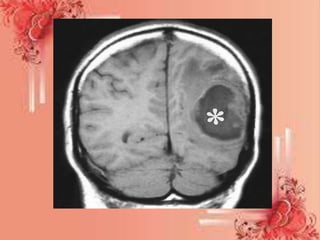

CT (computed tomography) scan -

In these imaging scans the abscess

will appear as one or more spots.

• CT-guided aspiration - this is a type of

needle biopsy. With the help of a CT

scan to guide him/her, the neurologist

inserts a needle into where the abscess is

and takes a sample of pus for analysis.

This will help determine what is causing

the abscess, and consequently, how to

treat it.

CT (computed tomography)scan - In these imaging scans the abscess will appear as one or more spots. • CT-guided aspiration - this is a type of needle biopsy. With the help of a CT scan to guide him/her, the neurologist inserts a needle into where the abscess is and takes a sample of pus for analysis. This will help determine what is causing the abscess, and consequently, how to treat it.